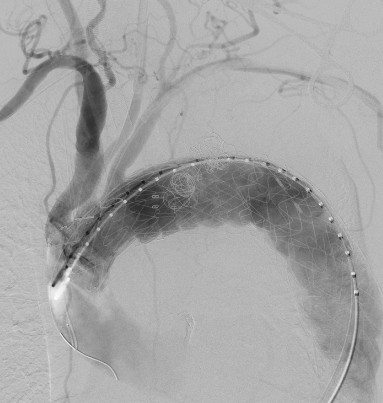

穿刺股动脉、切开颈动脉、肱动脉建立入路,超选内漏口、栓塞瘤腔,体外预开窗、重建弓上动脉......血管外科两组人马同时开工,有条不紊。在麻醉科林芩主任团队的密切配合下,一系列步骤紧张有序地进行着。手术持续了4个多小时,当最终的造影确认内漏完全封闭、假性动脉瘤成功隔绝,并且主动脉弓上的重要分支动脉血供良好的那一刻,血管外科团队成员都已忘却了身上几十斤的铅衣和满身的汗水。夏印主任和黎成金主任不禁对视一笑:“拆雷成功,又救了一条命。”

左颈总动脉、锁骨下动脉双开窗

瘤腔及内漏成功封堵,弓上分支动脉血流通畅